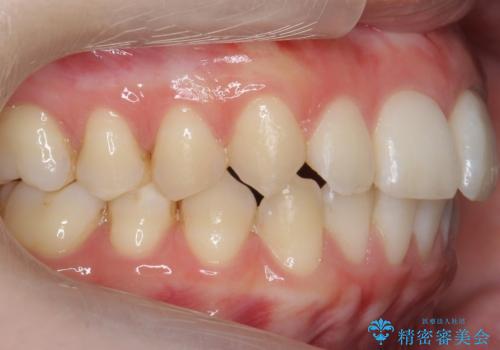

- 表面の着色を気にされて、ご来院されました。

お話しをしたところ、リーズナブルに短時間で綺麗にしたいとの事でした。

そこでPMTCの30分コースで、目立つ部分を中心に落としていきました。